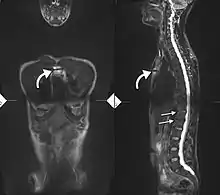

T1-weighted MRI with fat suppression after administration of gadolinium contrast showing sacroiliitis in a person with ankylosing spondylitis